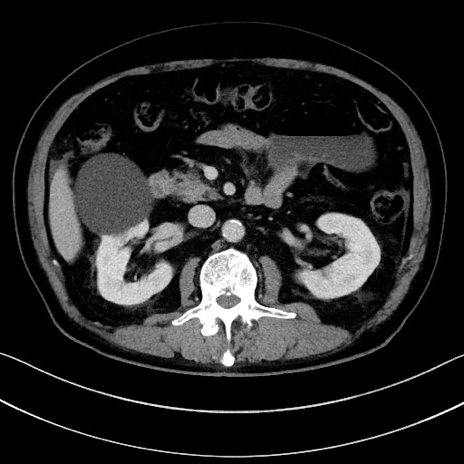

症例15(横断像)

【症例】70歳代男性

【主訴】腹痛

【現病歴】今朝から腹痛あり。全体的に痛い。特に左上の方。排ガスが今日はない。冷や汗が出る。

【既往歴】直腸癌術後

【身体所見】左側腹部〜上腹部に圧痛あり。腹膜刺激症状明らかなではない。軽度反跳痛。左下腹部に術後瘢痕あり。

【データ】WBC 7700、CRP 0.02